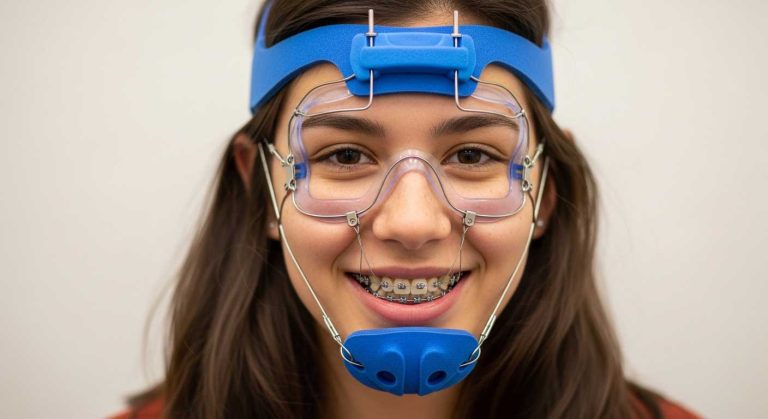

در کودکانی که دچار عقب ماندگی رشد فک بالا هستند، وسیع کننده کام اغلب در کنار دستگاه فیس ماسک برای تحریک رشد استخوان فک به جلو به کار میرود.

بررسی نمایید: فیس ماسک ارتودنسی